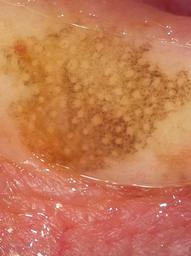

Biopsy-confirmed melanocytic and non-melanocytic skin lesions. This dataset includes over 500 melanomas. Many images have polarized and contact variants.